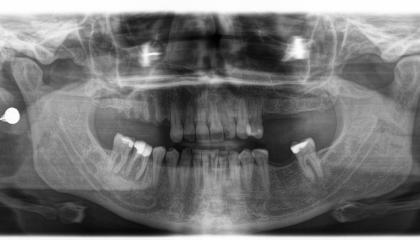

After

Zirconia bridge on Southern DC Implants